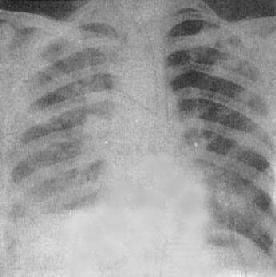

粟粒型肺结核病灶小,透视常难以辩认,故拟诊急性粟型肺结核时应摄片检查。病变早期整个肺野可呈毛玻璃样密度增高。约10日后可出现均匀分布的1.5~2mm大小、密度相同的粟粒状病灶,正常肺纹理常不能显示(图3-1-22)。经过适当治疗后。病灶可在数月内逐渐吸收,偶尔以纤维硬结或钙化而愈合。病变恶化时,可以发生病灶融合,表现为病灶增大,边缘模糊,甚至形成小片状或大片状影,并可干酪样化而形成空洞。

图3-1-22 急性粟粒型肺结核

两肺野布满粟粒状病灶,分布均匀,肺门大